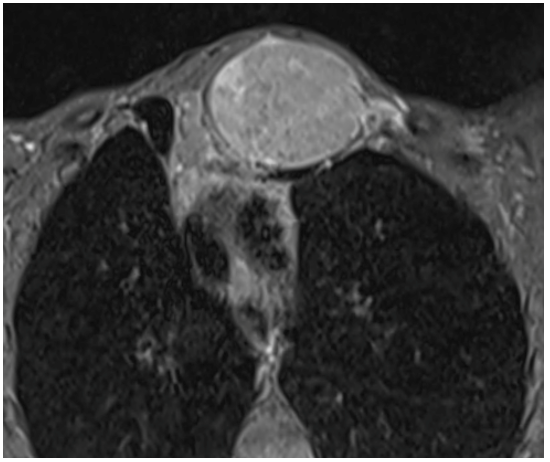

Hydatidosis Complications: Insights from a Rare Case of Simultaneous Intrapleural and Intrabronchial Rupture

Hadj Hsain Ihssan, Marrakchi Salma, Lahlou Chaimae, Boumerim Khaoula, Chehrestane Rachida, Allali Nazik, Chat Latifa and El Haddad Siham. 13(11): 01-05.